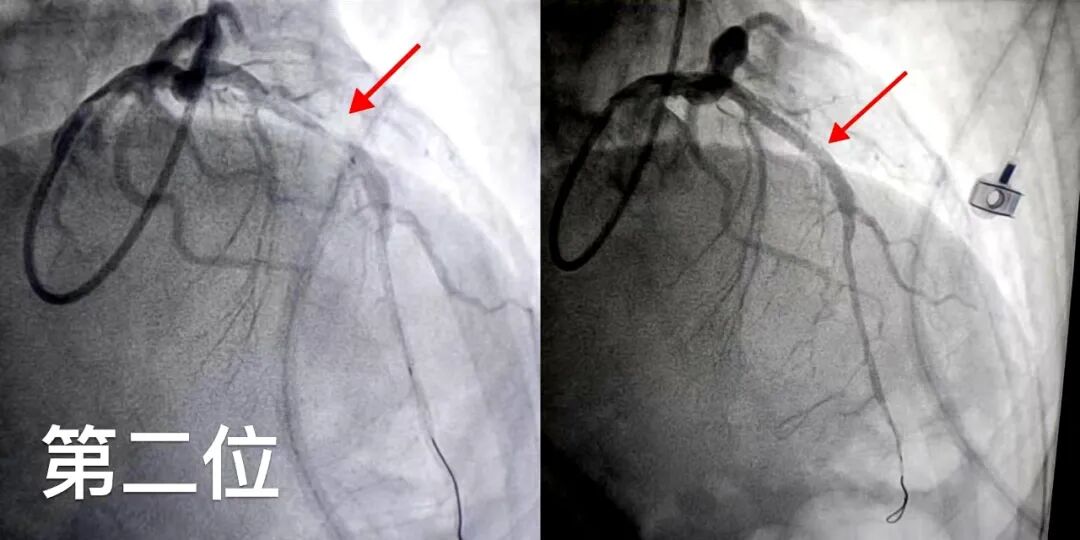

第一位患者为75岁女性,因胸痛持续5月、近1月加重来院就诊。心电图检查提示ST段压低,冠脉造影显示右冠状动脉存在严重病变。面对高龄、病程长的特点,心内科团队精准评估,成功实施介入治疗,为患者解除了长期的心绞痛困扰。